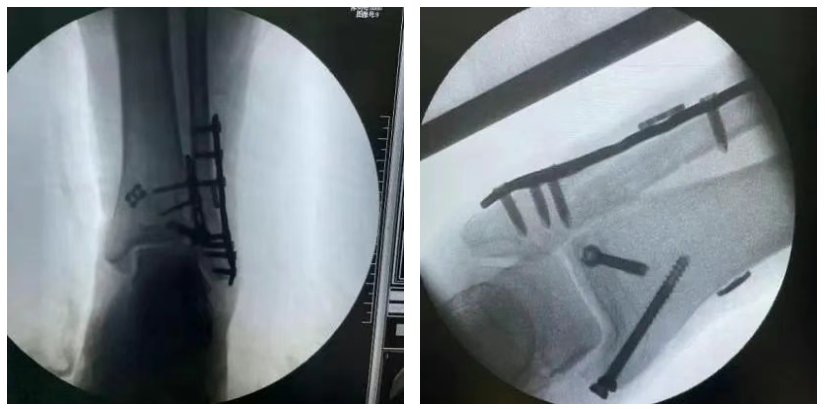

彈性固定方案

手術(shù)優(yōu)勢:

彈性固定,強度高,降低斷裂概率,更少并發(fā)癥

允許病人更早的進行非限制性負重和功能鍛煉

無需盡快二次取出

可調(diào)袢

型號:EBA0322

規(guī)格:12×4×1.5mm

蝶形板

型號:EBA0720

規(guī)格:14×1.5mm